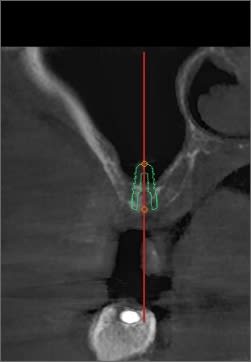

j aimerai avoir vos idées sur ce que j ai pu raté sur ce cas.

implant sur 16 avec summers prf biomat et à 2 mois l implant est dans la main du patient.

ca semblait bien en post op. image radio ok et bonne stabilité primaire.

en revanche pour le summers je suis pas trop d'accord. oui le cas est limite pour un summers mais je ne vois pas l impact que ca peut avoir sur ma situation. summers ou ouverture laterale, ça reste un comblement non? et d apres la 3d le resultat semblait pas trop mal, avec un dôme de biomat.

La théorie du Summers, c'est 5mm d'os minimum. Tu es donc plus que limite.

Ensuite le choix du type d'implant n'est probablement pas idéal si tu as utilisé le même que celui de la planification.

Ici c'est juste le micro-filetage du collet qui est au contact osseux alors que ce devraient être les spires plus profondes qui assurent la stabilité.